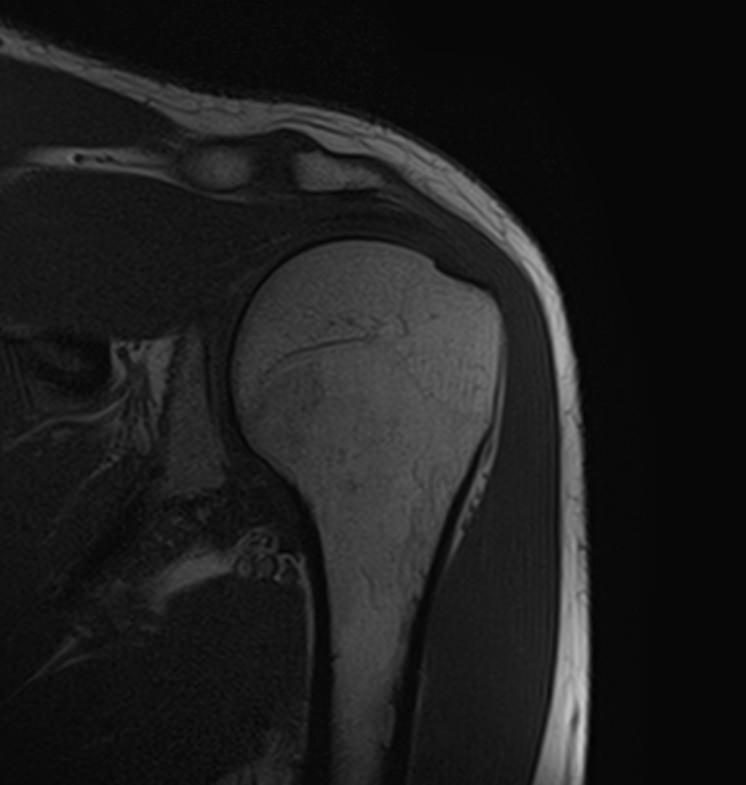

Для того, чтобы оценить состояние шейных позвонков с прилегающими тканями и одновременно визуализировать плечевой сустав, в нашей клинике выполняется комплексное обследование, включающее два протокола: МРТ шейного отдела позвоночника и МРТ плечевого сустава.

Метод МРТ позволяет оценить состояние всех анатомических областей шейного отдела позвоночника: костную структуру позвонков, спинной мозг с отходящими от него нервными корешками и окружающие мягкие ткани. Протокол обследования плечевого сустава включает оценку костной структуры, суставной капсулы, полости сустава с выстилающей его синовиальной оболочкой, связок, сухожилий, мышц и окружающих мягких тканей.